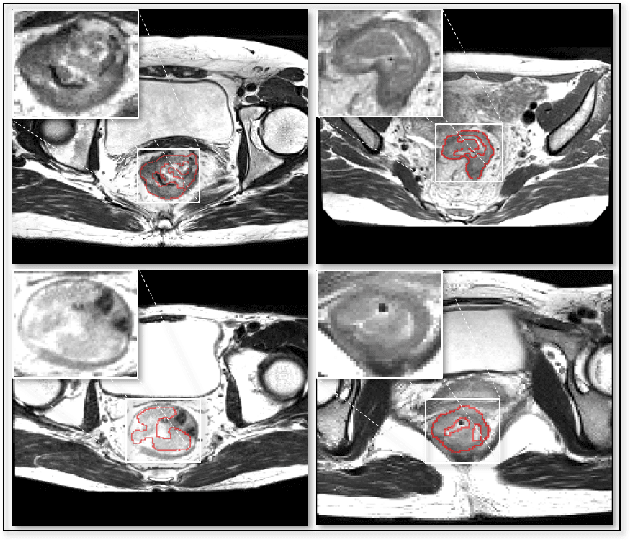

Abstract:Segmentation of colorectal cancerous regions from Magnetic Resonance (MR) images is a crucial procedure for radiotherapy which conventionally requires accurate delineation of tumour boundaries at an expense of labor, time and reproducibility. To address this important yet challenging task within the framework of performance-leading deep learning methods, regions of interest (RoIs) localization from large whole volume 3D images serves as a preceding operation that brings about multiple benefits in terms of speed, target completeness and reduction of false positives. Distinct from sliding window or discrete localization-segmentation based models, we propose a novel multi-task framework referred to as 3D RoI-aware U-Net (3D RU-Net), for RoI localization and intra-RoI segmentation where the two tasks share one backbone encoder network. With the region proposals from the encoder, we crop multi-level feature maps from the backbone network to form a GPU memory-efficient decoder for detail-preserving intra-RoI segmentation. To effectively train the model, we designed a Dice formulated loss function for the global-to-local multi-task learning procedure. Based on the promising efficiency gains demonstrated by the proposed method, we went on to ensemble multiple models to achieve even higher performance costing minor extra computational expensiveness. Extensive experiments were subsequently conducted on 64 cancerous cases with a four-fold cross-validation, and the results showed significant superiority in terms of accuracy and efficiency over conventional state-of-the art frameworks. In conclusion, the proposed method has a huge potential for extension to other 3D object segmentation tasks from medical images due to its inherent generalizability. The code for the proposed method is publicly available.